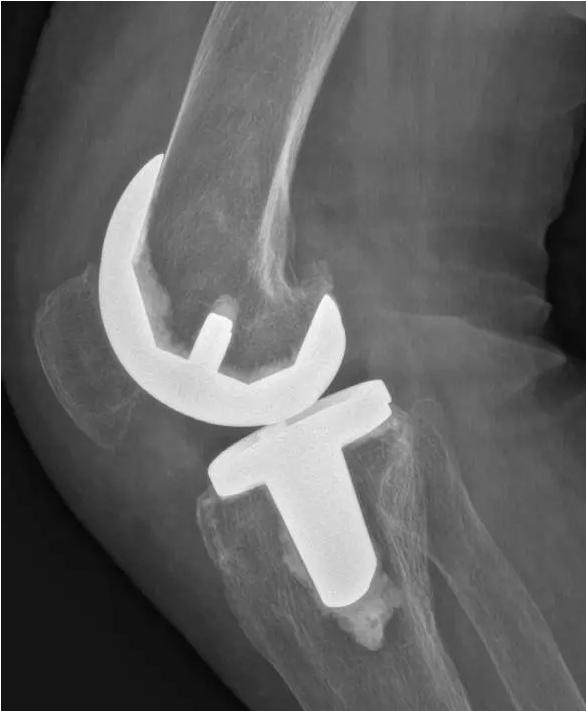

对于晚期(重度)骨关节炎,保守治疗无效时,要积极考虑手术治疗。目前效果最佳的手术方式即为关节置换手术,其他手术方式如关节融合手术等效果较关节置换术相差较大,已不在临床广泛使用。关节置换手术的目的是缓解患者疼痛,矫正关节畸形,恢复关节功能,恢复正常生活。对于老年人来说,积极的手术治疗可以有效恢复其日常生活,避免因疼痛及活动障碍导致患者扶拐或坐轮椅,有效减少因缺乏运动导致的心肺功能障碍及精神问题发生。经过几十年的发展,目前关节置换技术已十分成熟,临床上目前采用的微创技术,手术创伤小,术中出血非常少,术后第二天患者即可下地行走,三月之后即可恢复正常生活及功能。至于人工假体使用寿命,目前进口关节多为20-30年,能满足60-70岁患者的需求。需要关注的是,在行关节置换手术之后,患者仍需要进行积极的康复治疗,包括关节活动度及周围肌力的锻炼等,这样才能达到最佳的手术效果。

术后图如下: